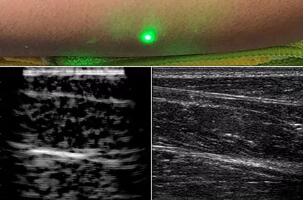

目前,研究人員已經(jīng)與健康的志愿者測試了他們的系統(tǒng):從半米遠(yuǎn)處掃描了他們的前臂,并將這些結(jié)果與傳統(tǒng)超聲的結(jié)果進行了比較。他們能夠觀察到深達6厘米的組織,并能看到肌肉,脂肪和骨頭,并報告其結(jié)果可與標(biāo)準(zhǔn)超聲相媲美。

研究人員用一種激光裝置測試了這個想法,該裝置使用一個波長為1,550納米的脈沖激光來產(chǎn)生聲波,并使用第二個連續(xù)激光,調(diào)諧到相同的波長以遠(yuǎn)程檢測反射的聲波。第二個激光器是靈敏的運動檢測器,可測量聲波從肌肉,脂肪和其他組織反射回來而引起的皮膚表面振動。反射的聲波產(chǎn)生的皮膚表面運動會導(dǎo)致激光頻率發(fā)生變化,這種變化可以測量。通過機械掃描人體上的激光,科學(xué)家可以獲取不同位置的數(shù)據(jù)并生成該區(qū)域的圖像。